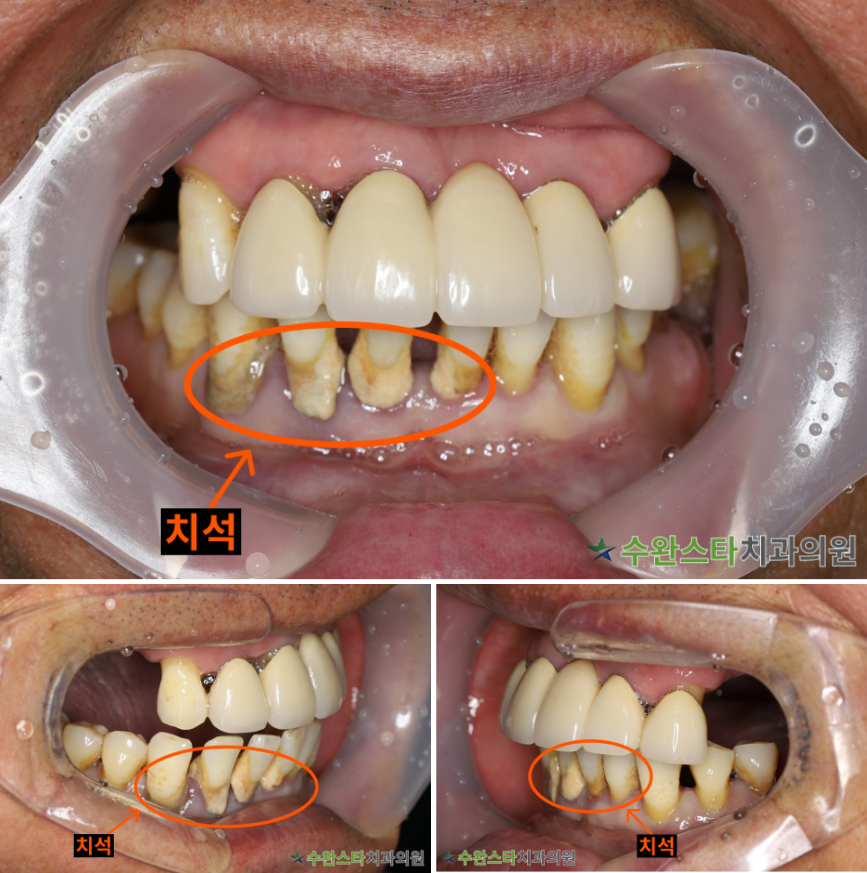

내원 시 상태

내원 시 환자분의

구강 내부 사진입니다.

어금니는 상실된 지

오래였고

아랫니에 치석이

많이 쌓여 잇몸뼈가

내려앉은 상태였습니다.